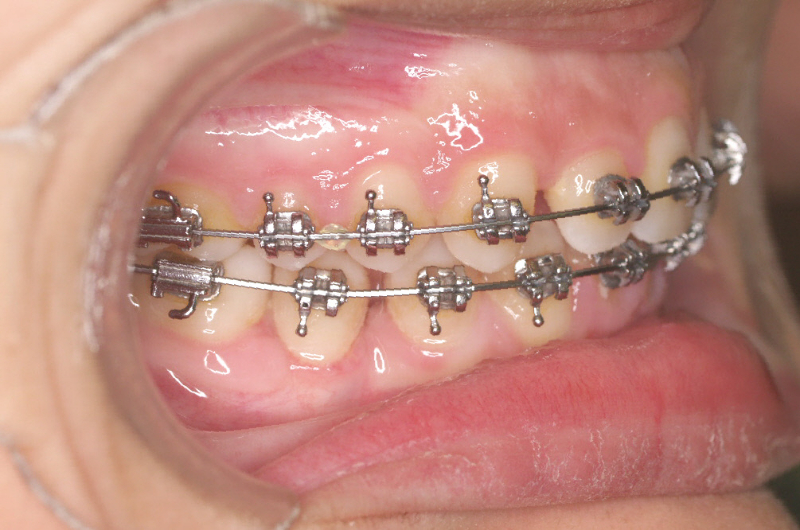

Premolar mandibular incluido + fenestración

45 incluido

Radiografía de final de tratamiento